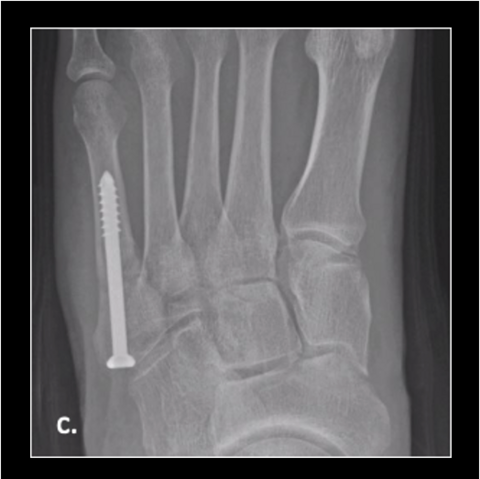

Figure 2c

Figure 2c. Here is the 30-year-old soldier’s foot 6 weeks post-injury.